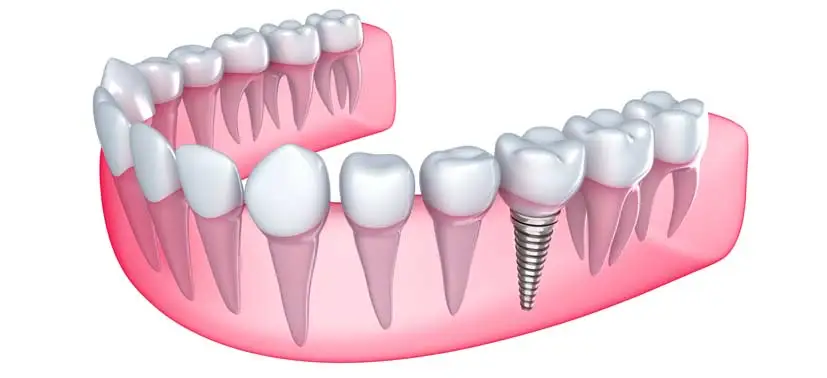

Dental implants are a great way to replace missing teeth and also provide a fixed solution to having removable partial or complete dentures. Dental implants are artificial roots and teeth (usually titanium) that are surgically placed into the upper or lower jaw bone by a dentist or Periodontist – a specialist of the gums and supporting bone. The teeth attached to implants are very natural looking and often enhance or restore a patient’s smile!

X-rays and impressions (molds) are taken of the jaw and teeth to determine bone, gum tissue, and spacing available for an implant. While the area is numb, the implant will be surgically placed into the bone and allowed to heal and integrate itself onto the bone for up to 3-6 months. The post and anchor are already attached and placed at the same time.

After several weeks of healing the artificial teeth are made and fitted to the post portion of the anchor. After a healing period, the artificial teeth are securely attached to the implant, providing excellent stability and comfort to the patient.